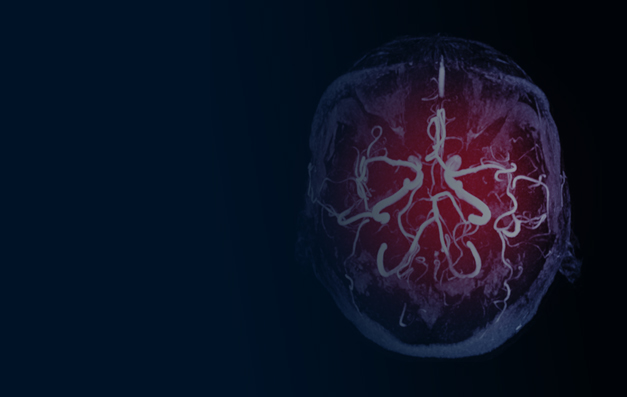

Acute ischemic stroke (AIS) represents a leading cause of death and long-term disability in the United States. In the pre-hospital management of AIS patients, it is critical to establish a workflow that reduces delays in time to treatment to promote positive patient outcomes.

Advanced strategies for the rapid diagnosis of AIS in the pre-hospital setting, in particular Mobile Stroke Units, can be employed to facilitate on-site treatment with thrombolytics, triage to the appropriate healthcare facility, decrease time to treatment for both thrombolytics and thrombectomy, and improve quality of life for AIS patients. The goal of this program is to educate a broad audience on advanced pre-hospital strategies to improve outcomes for patients with AIS.